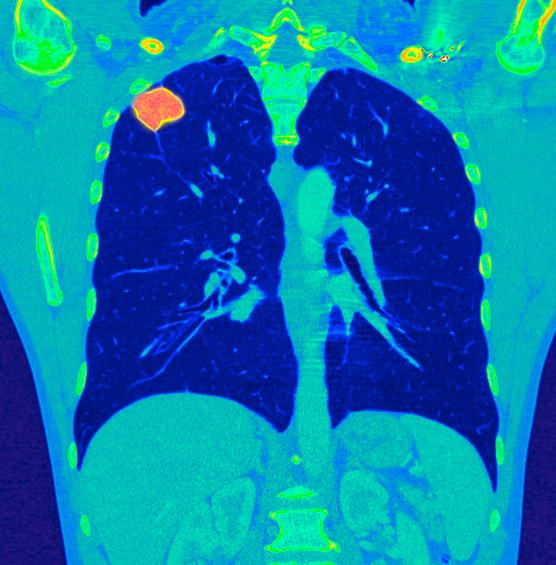

Pulmón, la necesidad de cribado

Este cáncer es el segundo más común en hombres, y el tercero en mujeres, en quienes su incidencia se está disparando: +5% anual desde 1990, mientras que en hombres está descendiendo levemente. “Dentro de uno o dos años, el cáncer de pulmón habrá superado al cáncer de mama en términos de mortalidad entre las mujeres”, advierte Sébastien Couraud, neumólogo y oncólogo de los Hospices Civils de Lyon. En 2018 se descontaron 10.300 muertes del primero y 12.100 del segundo. Según el Sr. Couraud, “No hay por qué imaginar que el número de casos femeninos no se suma al de hombres. Durante mucho tiempo este cáncer fue una enfermedad muy masculina, hoy es una enfermedad de ambos sexos..